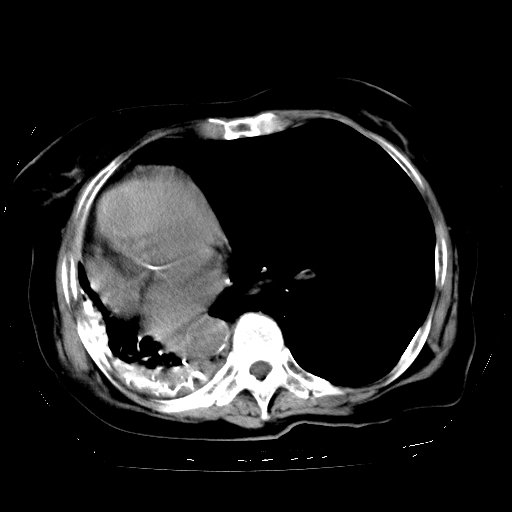

标题: CT23991:女,72岁,咳嗽、憋气一周。 [打印本页]

女,72岁,咳嗽、憋气一周,十年前曾患肺结核及胸膜结核。

右侧毁损肺,右侧纵隔疝

右侧毁损肺,右侧纵隔疝,左肺代偿!

1.右侧损毁肺伴胸膜钙化,2.左肺小结节灶,良性可能大,注意复查。3.肝脏左叶囊肿。4.先天性一侧肺不发育待出外(右侧胸廓无明显塌陷)。对比原片应该非常有帮助。